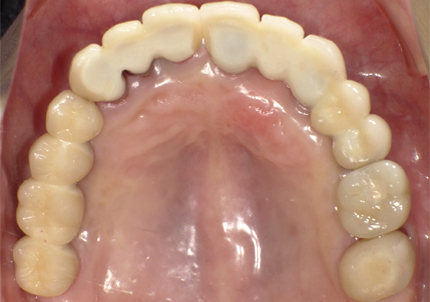

1.初診時口腔内(2007年6月30日)

↑ 2007年6月30日(初診)